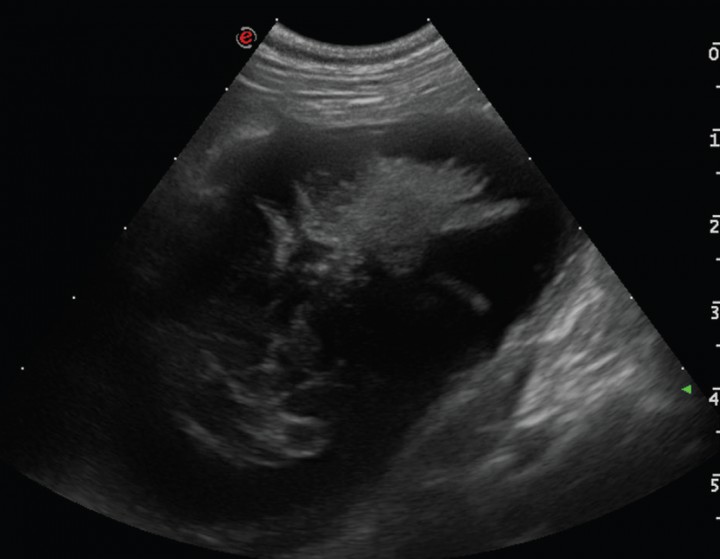

La ecogenicidad del parénquima hepático fue normal en la mayoría de los casos [58,8 % (21/37)], se visualizó hipoecogénico de manera difusa en el 18,9 % (7/37), hiperecogénico en el 13,5 % (5/37) y heterogéneo en el 10,8% (4/37). Se apreció una ligera efusión peritoneal en 4/37 casos (10,8%) y el peritoneo se encontraba aumentado de ecogenicidad en 4/37 casos (10,8 %); los dos casos de rotura de pared biliar (Fig. 9) presentaban ambas alteraciones, correspondiéndose la efusión peritoneal con un exudado.

<p>Imagen ecográfica de la vesícula biliar en corte transversal de un Chihuahua hembra de 5 años que presentaba vómitos, letargia y dolor abdominal. (A) Se visualiza la vesícula biliar aumentada de tamaño, con la pared irregular y engrosada, con contenido ecogénico inmóvil (mucocele biliar de Tipo IV). (B) Además se observaba el peritoneo adyacente hiperecogénico y presencia de líquido libre, siendo el diagnóstico definitivo rotura de la pared de la vesícula biliar y peritonitis focal.</p>

Figura 9

Imagen ecográfica de la vesícula biliar en corte transversal de un Chihuahua hembra de 5 años que presentaba vómitos, letargia y dolor abdominal. (A) Se visualiza la vesícula biliar aumentada de tamaño, con la pared irregular y engrosada, con contenido ecogénico inmóvil (mucocele biliar de Tipo IV). (B) Además se observaba el peritoneo adyacente hiperecogénico y presencia de líquido libre, siendo el diagnóstico definitivo rotura de la pared de la vesícula biliar y peritonitis focal.